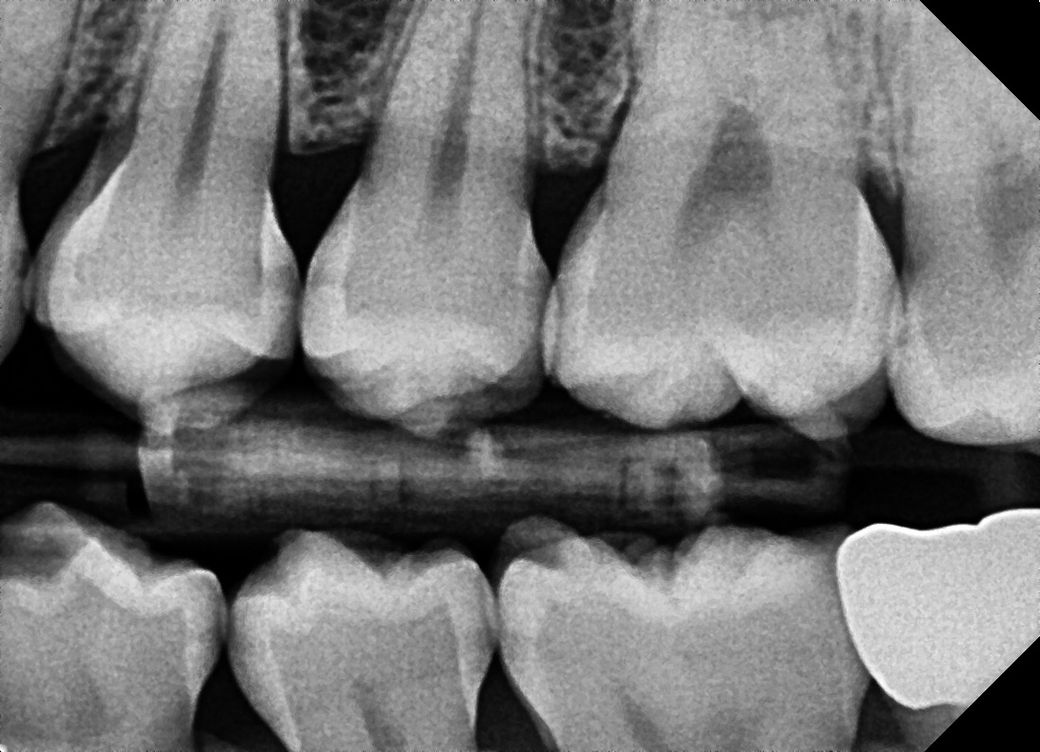

치과 의견이 너무 다릅니다.. 인접면 충치 관련 알려주세요

사진도 제일 많이 찍고 엑스레이사진이 제 주관상 가장 좀 선명?했습니다 인접면 충치가 9개 정도 모인다고 최소 198만원에서 271만원으로 인레인, 레진 치료를 해야한다고 합니다

사진은 a치과 엑스레이 사진입니다!

엑스레이 상으로는 인접면에 충치가 많이 있는걸로 보입니다. 일단 3개월정도 관리를 해보고 그때 가셔서 충치가 진행되면 치료를 진행하시고 관리가 잘되면 계속해서 관리를 해볼것같습니다.

정확한 검사는 따로 해봐야 겠으나 사진상으로는 명확히 충치가 여러군데에서 진행되고 있습니다.

방사선 사진상으로는 작은 충치가 보이긴 하지만 정확한 확인을 위해서는 육안으로 확인을 해야 합니다. 하지만 방사선 사진상으로는 그렇게 큰 충치는 보이지 않습니다.

B 치과 말이 맞습니다. 충치 조금 있는 것은 지켜 보다가 더 진행되면 해도 됩니다. 아마도 A치과는 상담원이 상담했을 가능성도 있습니다.